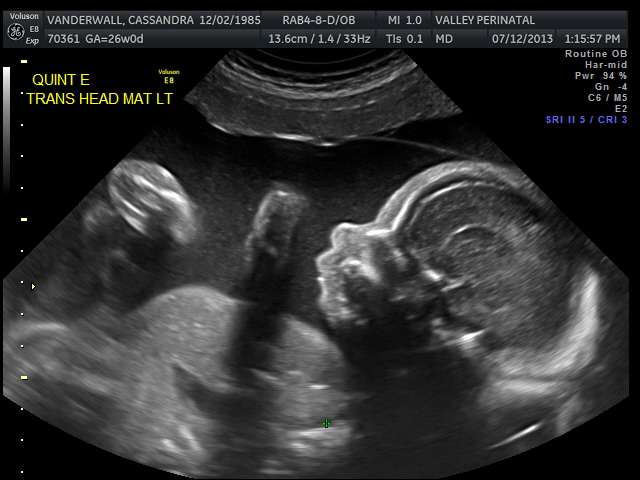

Friday we surpassed yet another milestone! The babies have been cooking for 7 months, which means we are now above the average gestational age for quintuplets. All of the babies were measured on Friday and they are all measuring within a day or two of the recommended size for babies at this point in pregnancy.

The biggest one in the bunch is Baby B at 2lbs and 12oz at the 62nd percentile. Little Elle Rose (Baby E) is the munchkin, but not by much as baby D and Theo (baby A) are also the same weight (2 ½ lbs) but just a bit longer. At this rate, when the baby’s are measured again at 32 weeks they will be about 1lb heavier each. Let’s just hope this Mama can keep up!

All of their organs (kidneys, bladders, hearts, brains, stomachs) look great and are also appropriate sizes. The blood flow to Elle has improved and has stabilized. All heart rates remain within normal limits, and are often on the higher side, which is probably because they just can’t sit still. We are truly excited to meet our little wiggle worms!